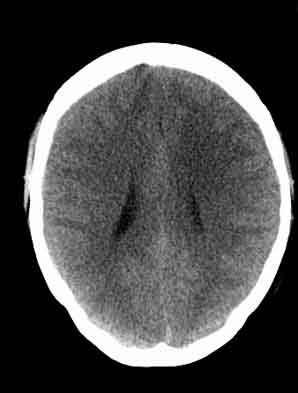

患者,女,29,头痛呕吐2月余,已建议增强或mri进检。

脑沟裂消失,脑白质密度似有减低,考虑脑炎。

大脑表面脑沟裂消失,颅压高的表现,经常遇到这样的现象,都没有一个明确的结论,望高人指点。

脑沟裂消失,脑白质密度似有减低,考虑脑炎。期待结果验证。